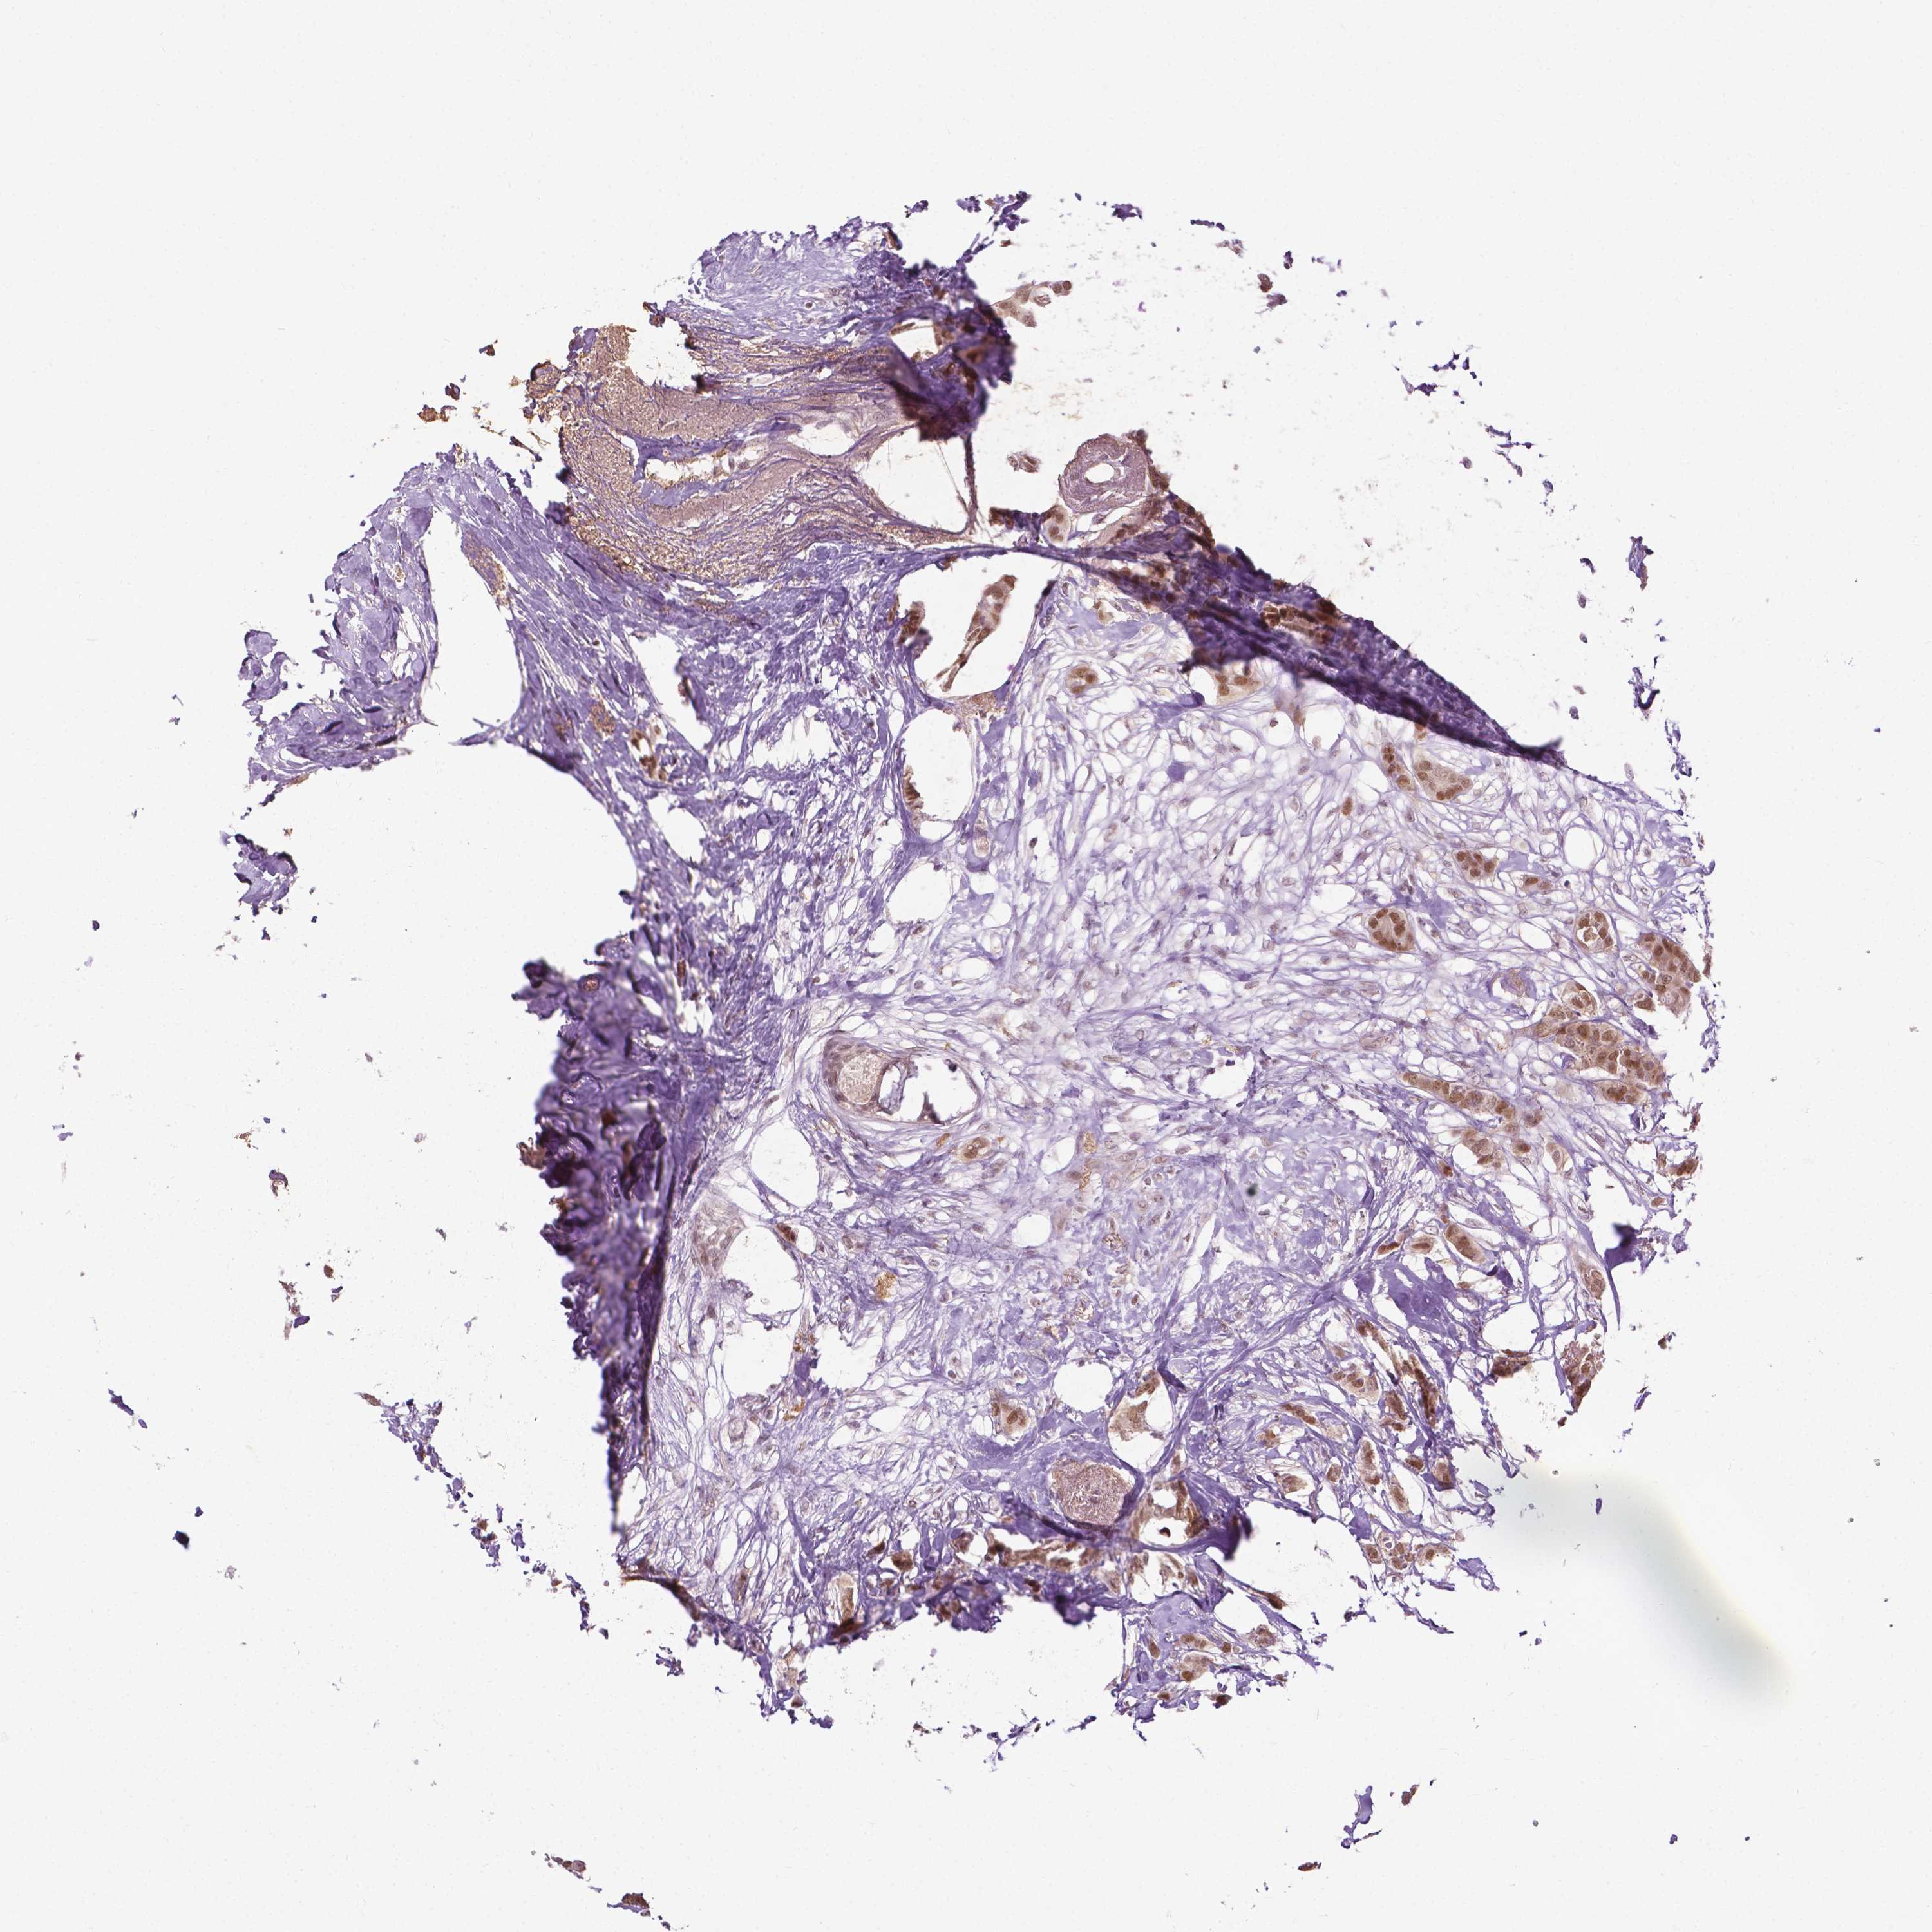

CANCER BREAST CANCER Show tissue menu

BRCA TCGA BRCA VALIDATION PROTEIN EXPRESSION